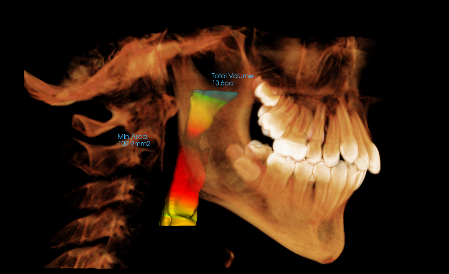

Airway-focused orthodontics looks beyond straight teeth to consider how jaw development, tongue posture, and bite alignment influence breathing and sleep. In both children and adults, orthodontic care can play an important role in supporting proper airflow by creating space for the tongue, optimizing jaw position, and promoting nasal breathing.

Rather than treating symptoms alone, airway-focused orthodontics considers the structure of the face and jaws as part of overall health. This approach is especially important during growth, but it can also benefit adults experiencing chronic mouth breathing, snoring, or orthodontic relapse.

Orthodontic treatment can influence airway health by addressing the structure and alignment of the jaws and teeth. When properly planned, orthodontics may help support breathing by:

- Expanding narrow dental arches

- Creating appropriate space for the tongue

- Improving bite alignment

- Encouraging nasal breathing patterns

- Supporting balanced facial development

Palatal expansion is one of the most impactful early interventions for growing kids. The upper jaw, when expanded at the proper age (typically 5–10 years old), will not only create more space for teeth, but transform the size and shape of the roof of the mouth — which provides space for optimal tongue function and increases nasal airway volume.